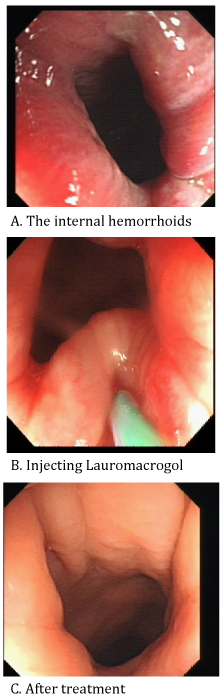

Figure 1 Video: colonoscopic sclerotherapy for bleeding internal hemorrhoids with lauromacrogol.

The procedure of the lauromacrogol sclerotherapy.